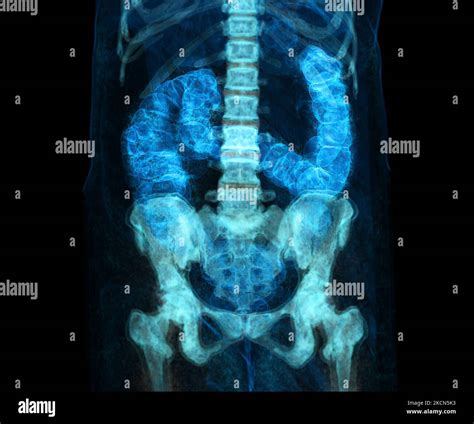

Le cancer du côlon, également connu sous le nom de cancer colorectal, est l'une des pathologies les plus répandues et les plus préoccupantes dans le monde. Comprendre la maladie nécessite souvent de visualiser les changements internes qui surviennent dans l'organisme. Bien que la recherche d'une Cancer Du Colon Image puisse être utile pour comprendre le processus pathologique, il est essentiel de consulter des professionnels de santé pour un diagnostic précis. Cette maladie se développe généralement à partir de petites excroissances appelées polypes qui, avec le temps, peuvent devenir cancéreuses. Une détection précoce est le facteur déterminant pour améliorer le pronostic vital et augmenter les chances de guérison.

Le cancer du côlon prend naissance dans le gros intestin. Le processus commence souvent par l'apparition de polypes adénomateux, des masses bénignes qui se forment sur la paroi interne du côlon. Si ces polypes ne sont pas détectés et retirés à temps, certains peuvent subir des mutations génétiques et se transformer en cellules cancéreuses. Une Cancer Du Colon Image permet souvent aux médecins d'illustrer la progression de ces lésions, allant d'un simple polype à une tumeur envahissante.

La progression est généralement lente, ce qui offre une fenêtre d'opportunité cruciale pour le dépistage. En observant l'aspect visuel des tissus lors d'une coloscopie, les gastro-entérologues peuvent identifier les zones suspectes, prélever des échantillons (biopsies) et même retirer les polypes précancéreux, stoppant ainsi la maladie avant qu'elle ne devienne invasive.

La technologie moderne a radicalement transformé la manière dont nous visualisons le cancer colorectal. Au-delà de la simple coloscopie optique, des techniques comme la coloscopie virtuelle (scanner haute résolution) permettent de reconstruire des images tridimensionnelles du côlon. Ces outils offrent une vision précise de la structure interne sans avoir recours à une procédure invasive immédiate. Ces avancées permettent non seulement une détection plus fine, mais aussi une personnalisation des traitements en fonction de la morphologie et de l'étendue exacte de la lésion.